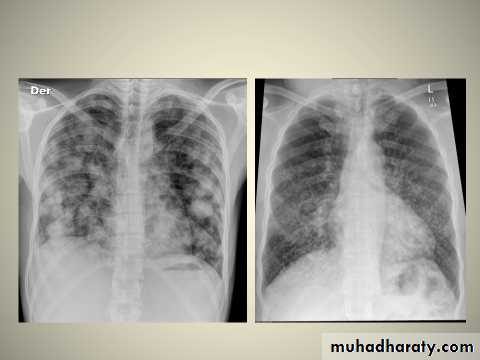

Multi-focal consolidation

Multiple areas of opacity seen throughout the lung most often is due to bronchopneumonia, starting from bronchi and spreading outwards. Usually ill defined with peripheral distribution. Neoplasms such as a primary malignancy or metastasis can also cause this picture.

Bronchopneumonia (also sometimes known as lobular pneumonia ) is a radiological pattern associated with suppurative peribronchiolar inflammation and subsequent patchy consolidation of one or more secondary lobules of a lung in response to a bacterial pneumonia.